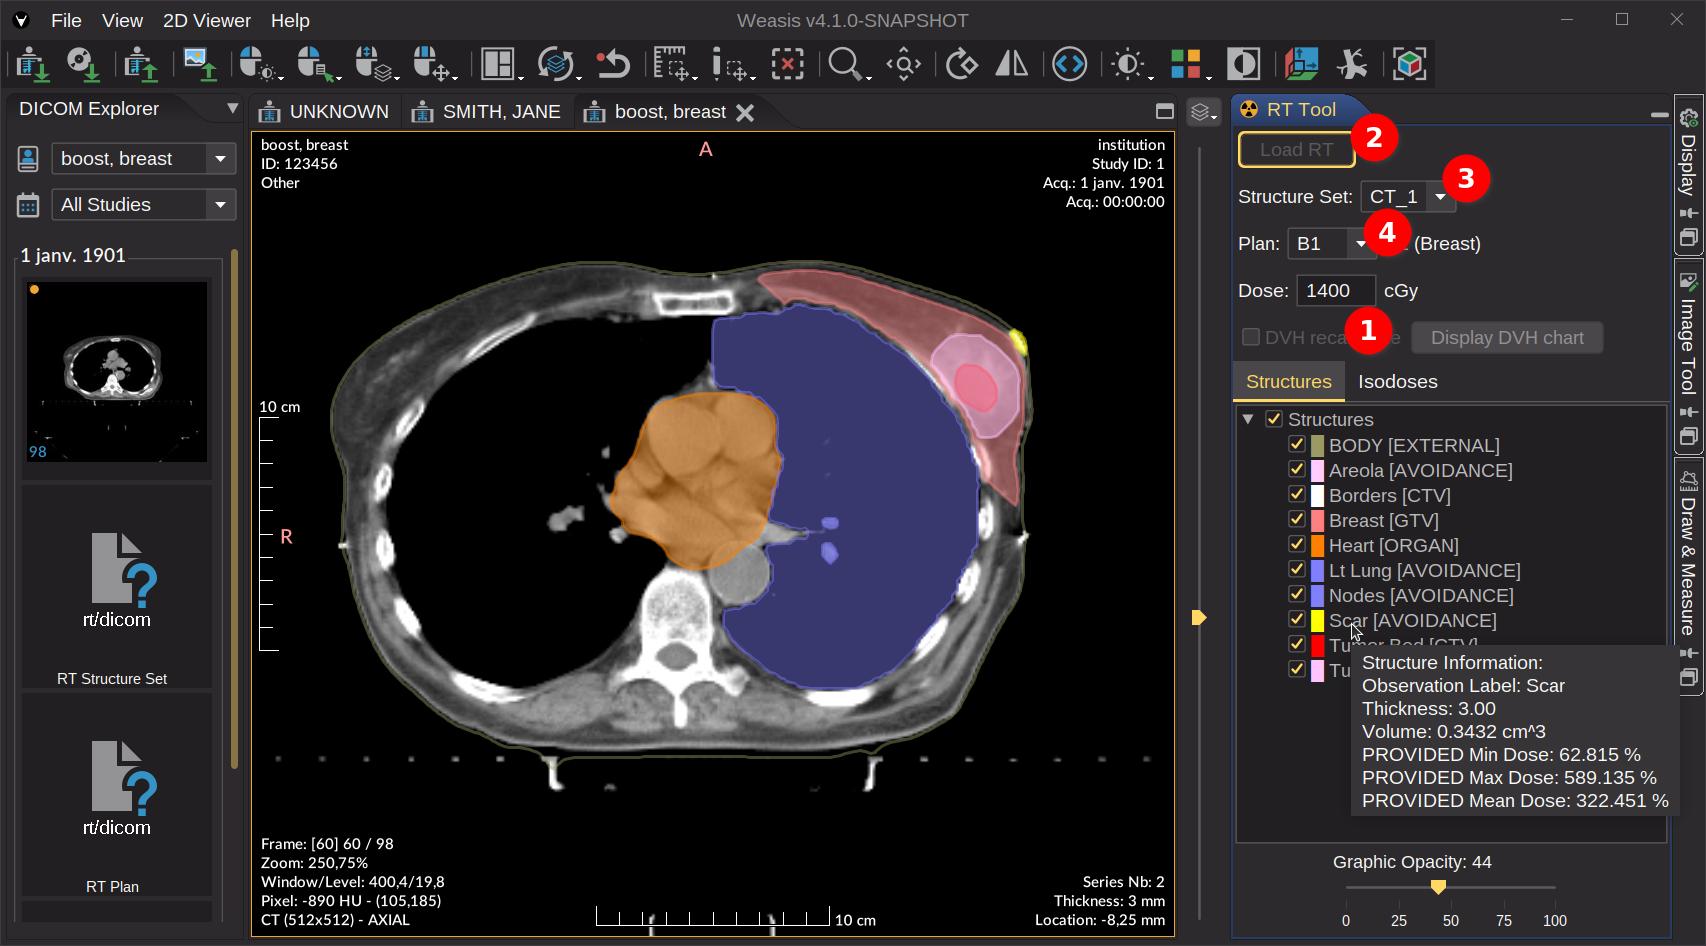

Enhance care with our medical Python Library Rt Dicom Monaco gallery of comprehensive galleries of therapeutic images. medically documenting photography, images, and pictures. designed to support medical professionals. Discover high-resolution Python Library Rt Dicom Monaco images optimized for various applications. Suitable for various applications including web design, social media, personal projects, and digital content creation All Python Library Rt Dicom Monaco images are available in high resolution with professional-grade quality, optimized for both digital and print applications, and include comprehensive metadata for easy organization and usage. Discover the perfect Python Library Rt Dicom Monaco images to enhance your visual communication needs. Our Python Library Rt Dicom Monaco database continuously expands with fresh, relevant content from skilled photographers. Instant download capabilities enable immediate access to chosen Python Library Rt Dicom Monaco images. Diverse style options within the Python Library Rt Dicom Monaco collection suit various aesthetic preferences. The Python Library Rt Dicom Monaco archive serves professionals, educators, and creatives across diverse industries. Regular updates keep the Python Library Rt Dicom Monaco collection current with contemporary trends and styles. Comprehensive tagging systems facilitate quick discovery of relevant Python Library Rt Dicom Monaco content. Time-saving browsing features help users locate ideal Python Library Rt Dicom Monaco images quickly.